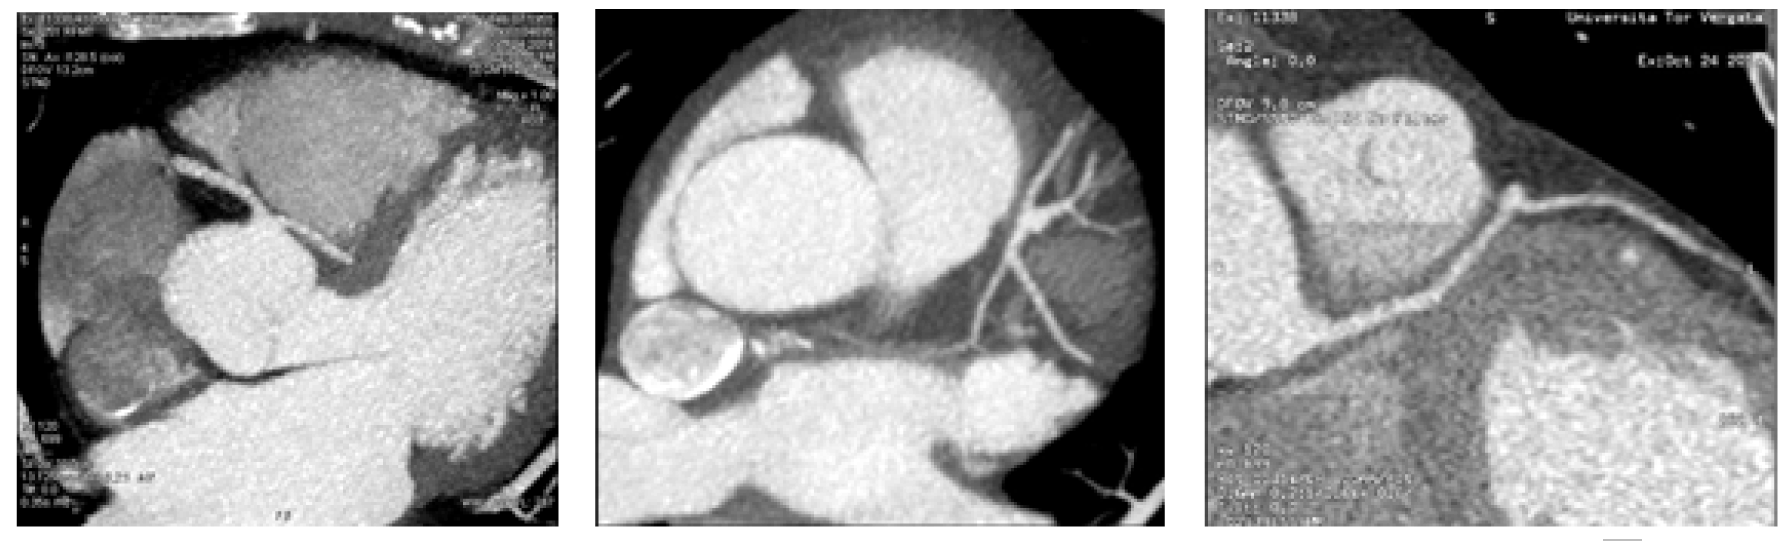

A 45-year-old male was admitted in our department with symptoms characterized by intermittent substernal chest discomfort non-provoked by exertion or emotional stress enlarging for over four months. The patient was a smoker of 7–8 packs of cigarettes per week for 10 years. Clinical history was negative for hypertension, diabetes mellitus, hyperlipidemia or family history of premature vascular disease and no risk factors for pulmonary embolism or respiratory distress. Physical examination showed normal blood pressure (BP: 128/88 mmHg), heart rate of 73 beats/min, no signs of vascular disease and normal cardiac examination. Initial laboratory tests showed no particular anomalies with normal blood levels of glucose and cholesterol (LDL: 103 mg/dl; HDL: 35 mg/dl; TG: 198 mg/dl). Resting electrocardiogram (ECG) showed normal sinus rhythm at 82 beats/min without anomalies in stress examination. Several echocardiographic examinations revealed a moderate enlargement of the left atrium; an apical form of left ventricular hypertrophy; a preserved left ventricular (LV) systolic function (LV ejection fraction, 57%); and moderate mitral valve regurgitation, with no abnormality of the mitral valve apparatus or of LV wall motion. Three months ago the patient had undergone coronary angiography evaluation which demonstrated an anomalous vascular anatomy with absence of coronary ostium in left cusp of the aortic valve and a single coronary artery (SCA) with origin by the right coronary cusp with one and only common trunk (CT) which gives rise to right coronary artery (RCA), left anterior descending (LAD) and diagonal artery, circumflex branch (CB) and the proximal left marginal artery (LMA). The RCA gives off the posterior descending artery (PDA) and the postero-lateral branch (PL). Significant flow-limiting stenosis was not detected with regular caliper representation of the three main coronary branches up to their distal segments. Contrast ventriculography confirmed the apical LVH and showed no wall motion abnormality. In our department, the patient underwent CT scanning, which confirmed the anomalous origin and course of coronary vessels showing also an inter-arterial course of the CT between the pulmonary artery and the aorta (Figure 1) (Figure 2). A 2-cm segment of the proximal-middle tract of the common trunk was embedded within the inter-ventricular septum, following an intramural course with a relative reduction of tunneled vessel (Figure 3). No significant atheromatous alterations have been highlighted, if we except for some parietal irregularities at LAD. Dipyridamole Tl-201 SPECT confirmed a perfusion abnormalities with reversible perfusion defects in the mid anteroseptal wall without an apical abnormality. The patient was admitted to cardiology center for further evaluation, treatment and periodical follow-up. |

Coronary angiography evaluation has demonstrated an anomalous vascular anatomy with absence of coronary ostium in left cusp of the aortic valve. Computed tomography (CT) scanning has confirmed the anomalous origin and course of coronary vessels showing also an inter-arterial course of the CT between the pulmonary artery and the aorta. A 2-cm segment of the proximal-middle tract of the CT was embedded within the inter-ventricular septum, following an intramural course with a relative reduction of tunneled vessel. Thin bridges can be not demonstrable angiography, so anatomic and panoramic CT-evaluation give more information especially if associated with functional evaluation. Knowledge of physiology, normal and variant anatomy, is most important in managing congenital and acquired disease, and variation in coronary arterial patterning is frequent. |